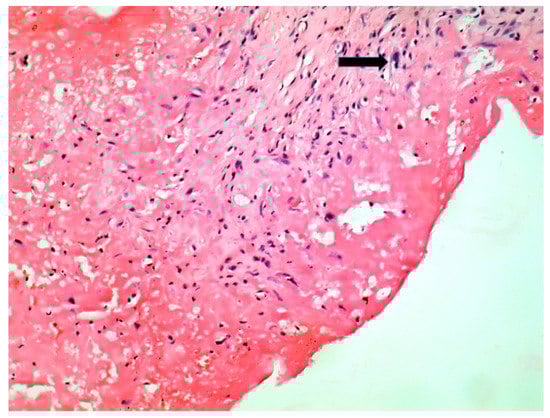

| Macroscopic | Mural trombi, Endocardial fibrosis [23] Monovalvular involvement Mixoid degeneration Valve ulceration or fibrinous mass No fibrin valve deposits [24,25] | Small, warty, sessile vegetations on valve flow surface [26] | Large or small vegetations on valve flow surface [27] | Small or absent vegetations, with a smooth nodular aspect [13] |

| Microscopic | Mixoid degeneration, mixed inflammatory pattern, granulomas, thickening of the small vessels wall [23] | Platelets, fibrin, red blood cells Repetitive process with fibroblastic organization and neovascularization [28] | Fibrin, polymorphonuclear inflammation and some bacterial colonies [29] | Minimal mononuclear inflammation, histiocytes, foamy macrophages and mild vascularization [30] Granulomas [31] Microabscesses; usually no microorganism, sometimes coccoid inclusions [23] Fibrosis, thrombosis and calcifications, mimicking degenerative damage [32] |